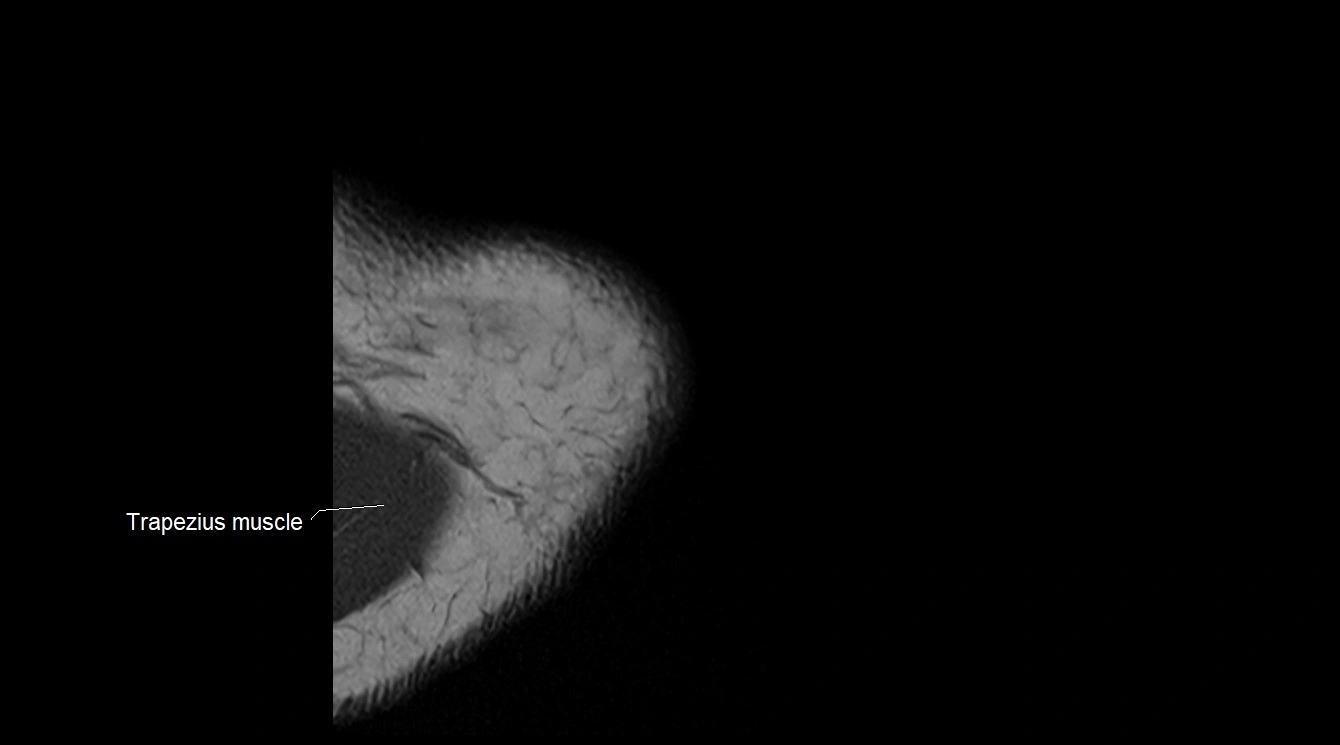

MRI image